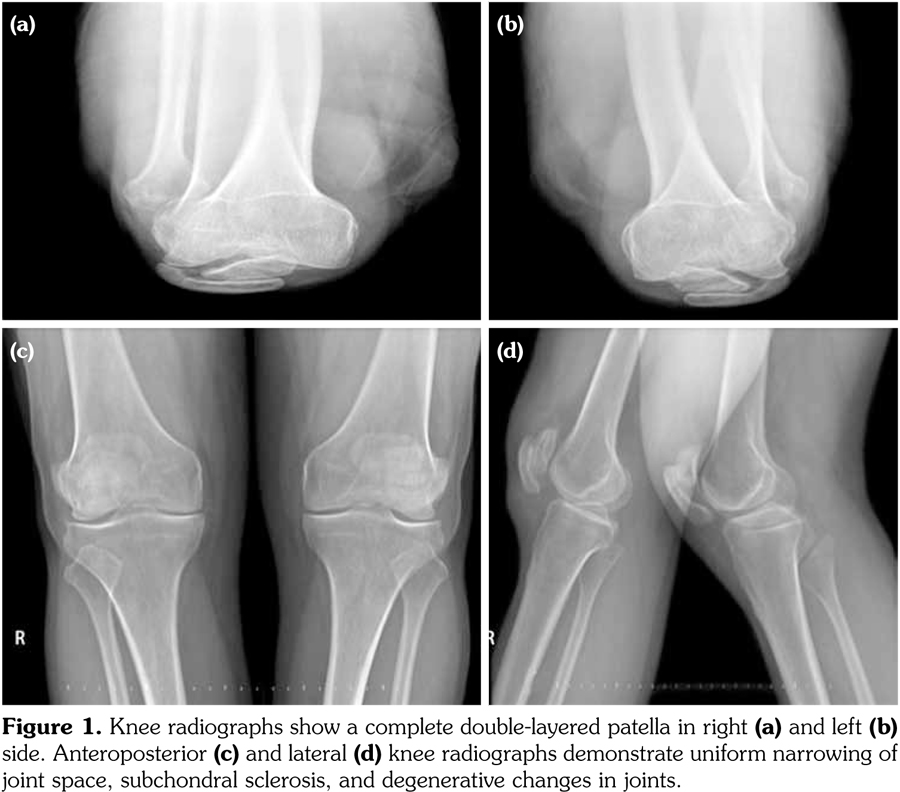

A 42-year-old male patient was examined due to gait difficulty and pain in hip and knee joints bilaterally and low back. He declared that he could walk independently, yet he had some difficulties in walking on undulating surfaces or climbing up stairs. Medical and family history was noncontributory. He was 168 cm tall and weighed 78 kg. Physical examination revealed severe restriction of range of motion in hip joints, crepitation in knee joints, hyperextension position of the first metacarpophalangeal joint, and deviation of the thumbs. Adam’s test for scoliosis was positive and lumbar motions were limited as well. Minimal joint effusion was detected in knee joints as well. Knee radiographies showed double- layered patella (DLP), generalized degenerative changes, scoliosis, and circumferential radiopaque lesion around the right hip joint (calcification of the iliopsoas bursa) (Figures 1 and 2). Magnetic resonance imaging designated the association between the quadriceps tendon and patella (Figure 3). Laboratory investigations including erythrocyte sedimentation rate and C-reactive protein, calcium, phosphate, and alkaline phosphatase levels were all within normal limits. Overall, the patient was diagnosed with secondary OA due to MED and referred to another center for further genetic analysis. A written informed consent was obtained from the patient.

Our patient with clunking in the knees had DLP bilaterally, which was reported previously in the literature.(8) DLP is a type of bipartite patella and caused by a septum dividing the patella into segments. It can be seen completely or partially. In general, DLP is associated with MED; however, it is reported in nondysplastic subjects as well.(9) Our patient had the total form of DLP. Magnetic resonance imaging showed that the distal part of the DLP was responsible for the extensor mechanism of the knees. This condition is important because the functional part could be indicative for a possible surgical procedure or functionality of the knee movements.